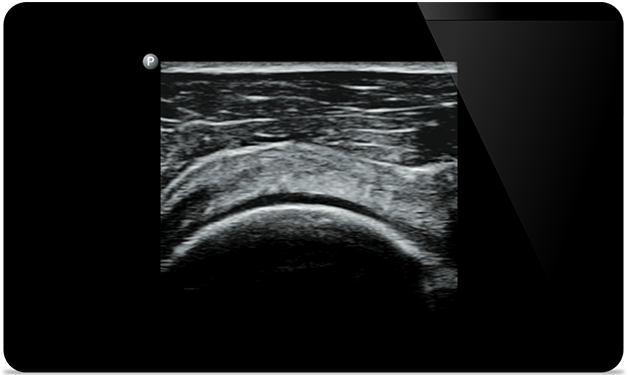

Lumify hilft Ihnen, die feinen Details in Muskeln, Gelenken, Bändern, Sehnen und Knorpeln zu erkennen, um Verletzungen präziser zu diagnostizieren.

Lumify unterstützt Sie bei der Beurteilung von Patienten von Kopf bis Fuß, sei es bei Plantarsehnenentzündung, Sehnenscheidenentzündung oder Schleimbeutelentzündung in der Patellasehne oder sogar bei Schulterinstabilität in der Rotatorenmanschette.

SonoCT verbessert die Gewebedarstellung und eliminiert Artefakte. So entstehen bei bis zu 94% der Patienten Bilder in besonders guter Qualität im Vergleich zu konventioneller Bildgebung.